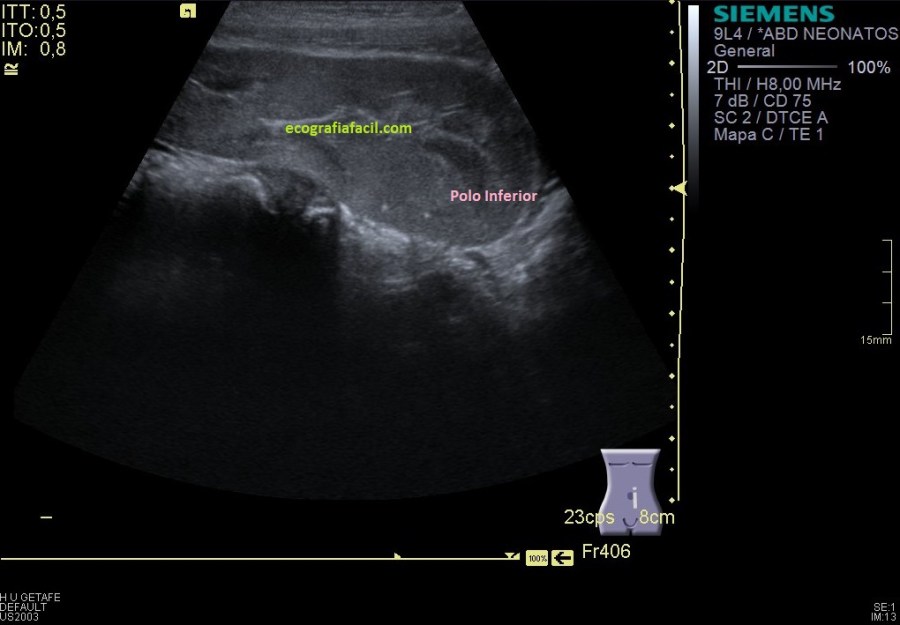

Como en la imagen 1 no he podido ver los polos, tengo que poder demostrarlos aunque tenga que estudiarlos de modo individual, polo superior en una,imagen 2 y polo inferior en otra, imagen 3.

Y nos quedaba buscar el polo superior, imagen 8, buscándolo nos encontramos que este polo superior está unido al polo inferior del RD, sí lo sabía, pero el protocolo de búsqueda de ambos polos renales individualizadamente te garantiza que este tipo de malformaciónes, tipo riñón en herradura, no se escapen. En este caso se ve fenomenal, como ambos polos están, unidos entre sí

Me viene genial este caso para hablarte de la resolución de la imagen, que depende de muchas cosas, te lo enlazo para que lo repases, pero quiero que hoy te quedes con la siguiente idea. Cuando realizamos ecografía, una parte vital del éxito de la prueba de la consecución de los hallazgos es la calidad de los equipos, su gama, es decir, si son de gama alta, media o baja y del estado general del equipo. Lógicamente, un equipo de gama alta te dará mejores imágenes, la comparación de la imagen 18 y 19 son muestra inequívoca de ello, misma paciente, mismo órgano, misma proyección, pero distinto equipo. Una imagen vale más que mil palabras, así que observa.

Entre la 16 y la 17 puedes ver, el mismo RD estudiado con sonda cónvex y sonda lineal, en el mismo instante, muchas veces, los niños están en esa edad en la que debes usar las dos sondas, porque son del tamaño intermedio que ni son pequeños para estudiarlos con la sonda lineal ni lo suficientemente grandes como para usar de baja frecuencia, por la calidad y la nitidez de imagen, siempre recomiendo usar en la medida de lo posible con sondas lineales de alta frecuencia, como norma general, siempre usaremos la frecuencia más alta disponible para el estudio que estemos ejecutando.